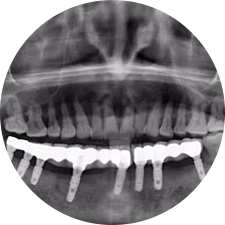

口腔種植是將人工牙根通過(guò)手術(shù)植入牙骨內(nèi),獲得牙槽骨牢固的支持,通過(guò)特殊的裝置和方式連接牙修復(fù)體,獲得與天然牙功能、結(jié)構(gòu)以及美觀相似的效果。

河北惟德口腔醫(yī)院擁有國(guó)內(nèi)豐富的半口/全口、即刻負(fù)重種植案例,十八年案例跟蹤分析,總結(jié)梳理出的各種不同類型的種植案例,Nobel種植體系針對(duì)半口/全口缺牙患者,通過(guò)4-8顆種植體可快速達(dá)到牙齒重建,不僅植入種植體較少,節(jié)省費(fèi)用,手術(shù)時(shí)間更短。

術(shù)前患者CBCT口掃1:1三維重建,模擬手術(shù)過(guò)程及預(yù)測(cè)術(shù)后治療效果,確定每顆植體植入的適合的種植位點(diǎn)、深度及角度,有效避免損傷頜骨重要解剖結(jié)構(gòu),提高手術(shù)準(zhǔn)確度與安全性。

Noble口腔種植體系基本不受年齡限制,適用于缺牙修復(fù),也適用于牙槽骨萎縮、骨質(zhì)疏松、高血壓、糖尿病、超高齡的患者,即種即用,只需少量微小種植體,便可輕松微痛快速重建全口咬合,特殊力學(xué)設(shè)計(jì),針對(duì)許多年紀(jì)較大,骨質(zhì)條件差,身體耐受力差的缺牙老人也能完成“即種即用”,受到廣泛好評(píng)。

惟德口腔種植體系是以患者感受為中心,取代傳統(tǒng)種植牙手術(shù)需要翻瓣、打孔、縫合,術(shù)前、術(shù)中、術(shù)后的繁復(fù)流程,采用3D導(dǎo)航微創(chuàng)準(zhǔn)確種植技術(shù),通過(guò)數(shù)字化CAD/CAM掃描技術(shù)獲得缺牙患者口腔數(shù)據(jù),以數(shù)據(jù)為基礎(chǔ)重建口腔模型進(jìn)行模擬種植。

術(shù)前將患者口內(nèi)的CBCT數(shù)據(jù)及咬合關(guān)系上傳到計(jì)算機(jī)中,建立1:1三維重建,模擬手術(shù)過(guò)程及預(yù)測(cè)術(shù)后治療效果,找出較佳種植位點(diǎn)、深度及角度,獲取實(shí)際種植體在頜骨內(nèi)的具體三維位置,有效避免損傷頜骨重要解剖結(jié)構(gòu),大大降低手術(shù)風(fēng)險(xiǎn),提升種植成功率。